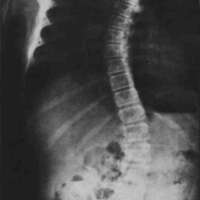

The orthotic management of idiopathic scoliosis (Fig. 1) over the years has employed a number of different orthotic systems. Included among them have been the Milwaukee and modified cervico-thoracolumbosacral orthoses (C.T.L.S.O.) as well as various prefabricated, modular, and custom fabricated thoracolumbosacral orthoses (T.L.S.O.).

Figure 1: